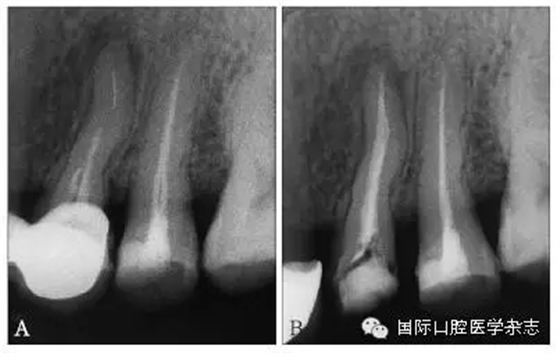

目前,對于分離器械周圍牙本質(zhì)厚度的評估以及取出后殘余牙本質(zhì)厚度的預(yù)測主要需借助影像學(xué)檢查,例如根尖片、錐形束CT(cone beamcomputed tomography,CBCT)圖像等。傳統(tǒng)的平行投照的根尖片無法反映三維立體結(jié)構(gòu),且往往存在解剖結(jié)構(gòu)影像的重疊,不利于臨床判斷,具有一定的局限性。多位學(xué)者[10]的研究表明:平行投照的根尖片會高估實(shí)際的牙本質(zhì)壁的厚度。一些學(xué)者[11-12]的研究表明:當(dāng)分離器械位于上頜第一磨牙近中根管時,采用成角投照(21°)的拍攝技術(shù)與平行投照技術(shù)得到的X線片相比,能更準(zhǔn)確地評估牙本質(zhì)的厚度,為分離器械取出與否提供指導(dǎo)(圖4)。近年來,CBCT在牙髓病學(xué)中的應(yīng)用越來越廣泛,由于CBCT能清楚地反映牙及牙根周圍組織的三維立體結(jié)構(gòu),為牙本質(zhì)厚度的評估與預(yù)測提供了可行性(圖5);因此,CBCT在器械分離的病例術(shù)前風(fēng)險評估方面具有較好的應(yīng)用前景。

A、B:采用平行投照技術(shù)獲得的圖像,模擬取出分離器械后殘余牙本質(zhì)的厚度,分離器械分別位于根管口下3 mm和5 mm;C、D:采用成角投照技術(shù)獲得的圖像,模擬取出分離器械后殘余牙本質(zhì)的厚度,分離器械分別位于根管口下3 mm和5 mm。

圖 4 平行投照與成角投照拍攝技術(shù)對牙本質(zhì)厚度的評估